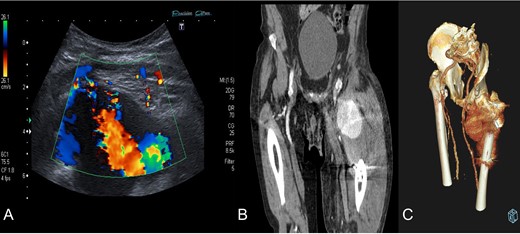

We present a case of an 80-year-old institutionalized man, who suffered an unstable intertrochanteric fracture of the left hip, type 31.A2.1 (AO-OTA) due to a low energy accident after falling from his own height. The patient previous medical history included bipolar disorder, hypertension, DM, and right inguinal herniorrhaphy surgery. The patient underwent closed reduction and internal fixation with an intramedullary nail type Gamma3 (Stryker Trauma GmbH Prof. Küntscher-Str. 1-5 24 232 Schönkirchen, Germany) of the fracture during the first 24 hours after injury. The surgical procedure was performed without any intraoperative complications. He was discharged from the hospital on the sixth postoperative day, asymptomatic, with a postoperative hematoma in the left thigh, walking with a walking frame, with a postoperative radiographic control showing a correct nail placement without alterations and with an hemoglobin value (HGB) of 10.7 g/dl and a hematocrit value (HCT) of 30.8%. On the 18th postoperative day, he suffered a fall after having a syncopal episode, so he went to the emergency room and was admitted to the hospital for study. The hematoma in his thigh was evolving correctly, and the radiographs remained unchanged with respect to the previous ones. He was discharged two days later. One month after surgery, he returned to the hospital due to persistent pain, volume increase and progressive hematoma in the left thigh. The blood analysis showed an anemia (HGB 9.5 g/dL, HCT 29%). The pedia pulse was present and the posterior tibial pulse was weaker than the contralateral but also present. An X-ray showed a superior and medial displacement of the lesser trochanter compared to previous radiographs and a medialization of the femoral artery, visible because it was calcified (Fig. 1). A Doppler ultrasound was performed showing a hypoechoic lesion with turbulent flow inside compatible with pseudoaneurysm at the level of the deep femoral artery or one of its branches. The study was completed with a CT angiography that confirmed the presence of a pseudoaneurysm of 7.3 × 6.7 × 6 cm at the level of the deep femoral artery at the beginning of the lateral circumflex branch (Fig. 2). At that time, the patient was referred to the Interventional Radiology Service. The vascular lesion was immediately treated by femoral transcatheter embolization with two distal coils in the lateral circumflex artery measuring 3 and 4 mm (Axium 3D Medtronic 9775 Toledo Way Irvine, CA 92 618 USA) and proximal embolization by a liquid embolic agent, Onyx 34 (Covidien 106-108 Rue la Boetie 75 008 Paris, France).

Diagnosis confirmation by Doppler ultrasound (A), shows hypoechoic lesion with turbulent flow inside with 5–6 cm of maximum diameter; and CT angiography (B) and three-dimensional reconstruction (C) that confirm a lateral circumflex artery pseudoaneurym branch of the deep femoral artery of 7,3 × 6,7 × 6 cm size.